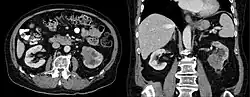

Collecting duct carcinoma

Collecting duct carcinoma (CDC) is a type of kidney cancer that originates in the papillary duct of the kidney. It is rare, accounting for 1-3% of all kidney cancers.[2] It is also recently described; a 2002 review found just 40 case reports worldwide.[3] Previously, due to its location, CDC was commonly diagnosed as renal cell carcinoma or a subtype of renal cell carcinoma.[4] However, CDC does not respond well to chemotherapy drugs used for renal cell carcinoma, and progresses and spreads more quickly.